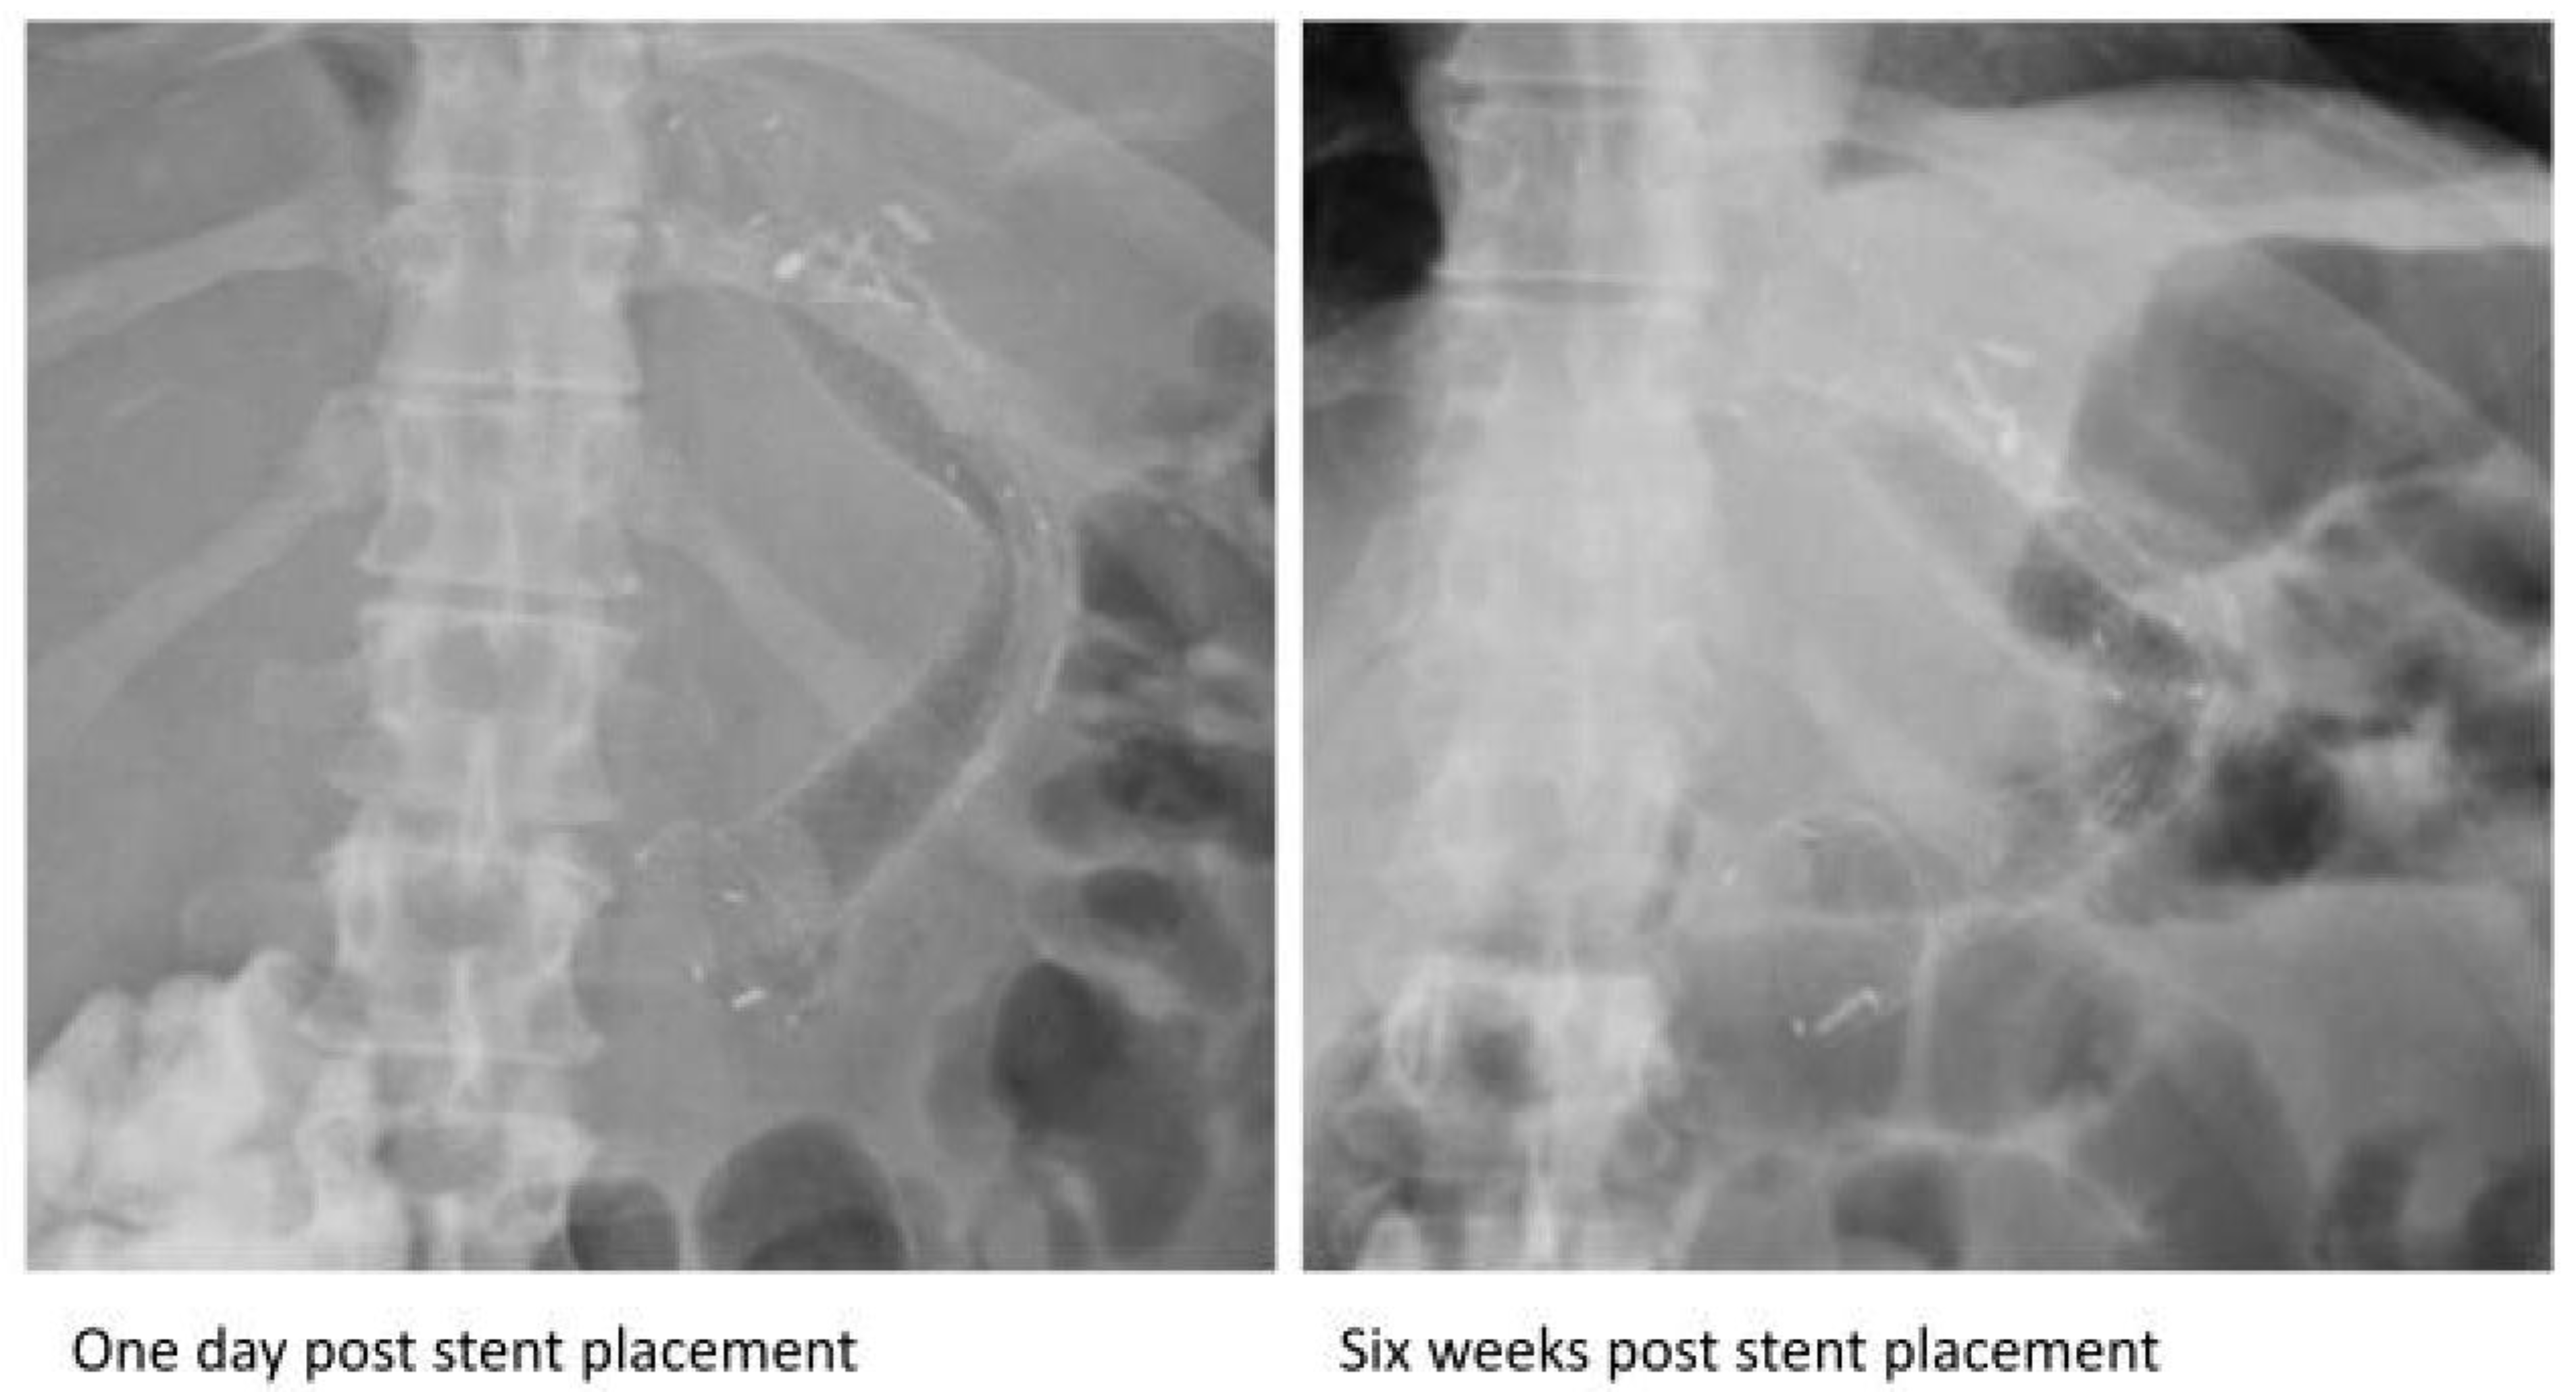

| Some cases were diagnosed by imaging [8,9,11,12,13,16,20,24,32] Most were diagnosed during or after endoscopic removal | All the SEMS fractured in vivo and were noted during or after endoscopic removal. | ||